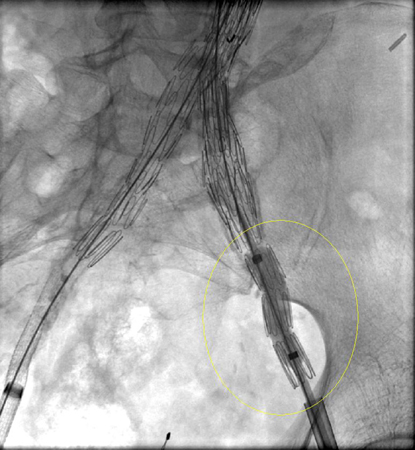

Abdominal aortic aneurysm

Type I endoleak at the distal left iliac anastomosis (leak encircled)

University of Michigan, specifically the cases of Dr Upchurch reflecting the Departments of Vascular Surgery and Radiology